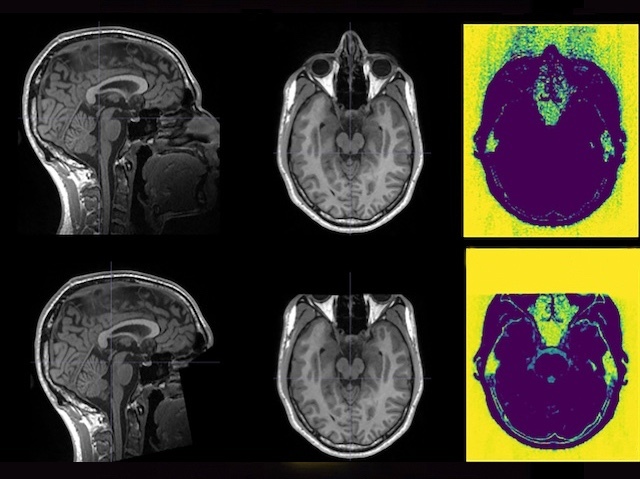

On the face of it, an MRI brain scan might not look much like a recognisable person, but removing facial features (pictured, bottom, with full scans above) is an essential step in ensuring that privacy is maintained when people’s scans are used in research. Altering images inevitably risks influencing their reliability, so researchers investigated how ‘defacing’ impacted human and automated quality assessments of a set of scans in an openly-available database. Trained human raters ranked the images as being of different quality when defaced – on average slightly higher – especially on lower quality scans. The bias was most pronounced in the most experienced ranker’s judgements, suggesting preconceptions that have accumulated over time. But automated computer quality assessment was unaffected by defacing. The researchers suggest ensuring quality checks happen before images are defaced to avoid bias creeping in at the early stage of processing that might affect analysis and research outcomes later.